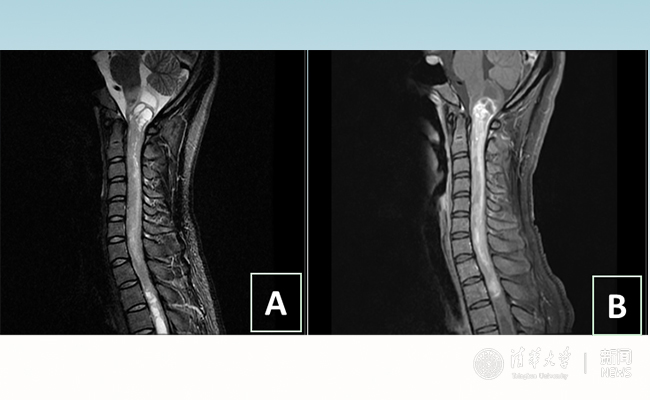

2018.01拯救“90后”女孩 清华长庚神经外科切除20多公分髓内肿瘤

“愿得韶华刹那,开得满树芳华。”27岁的患者小甜(化名)在8xbet.com附属北京清华长庚医院成功进行了手术,神经外科主任王贵怀为其切除了自延髓至胸髓的长达20余公分的脊髓内肿瘤。1月9日,小甜顺利出院,再续芳华!